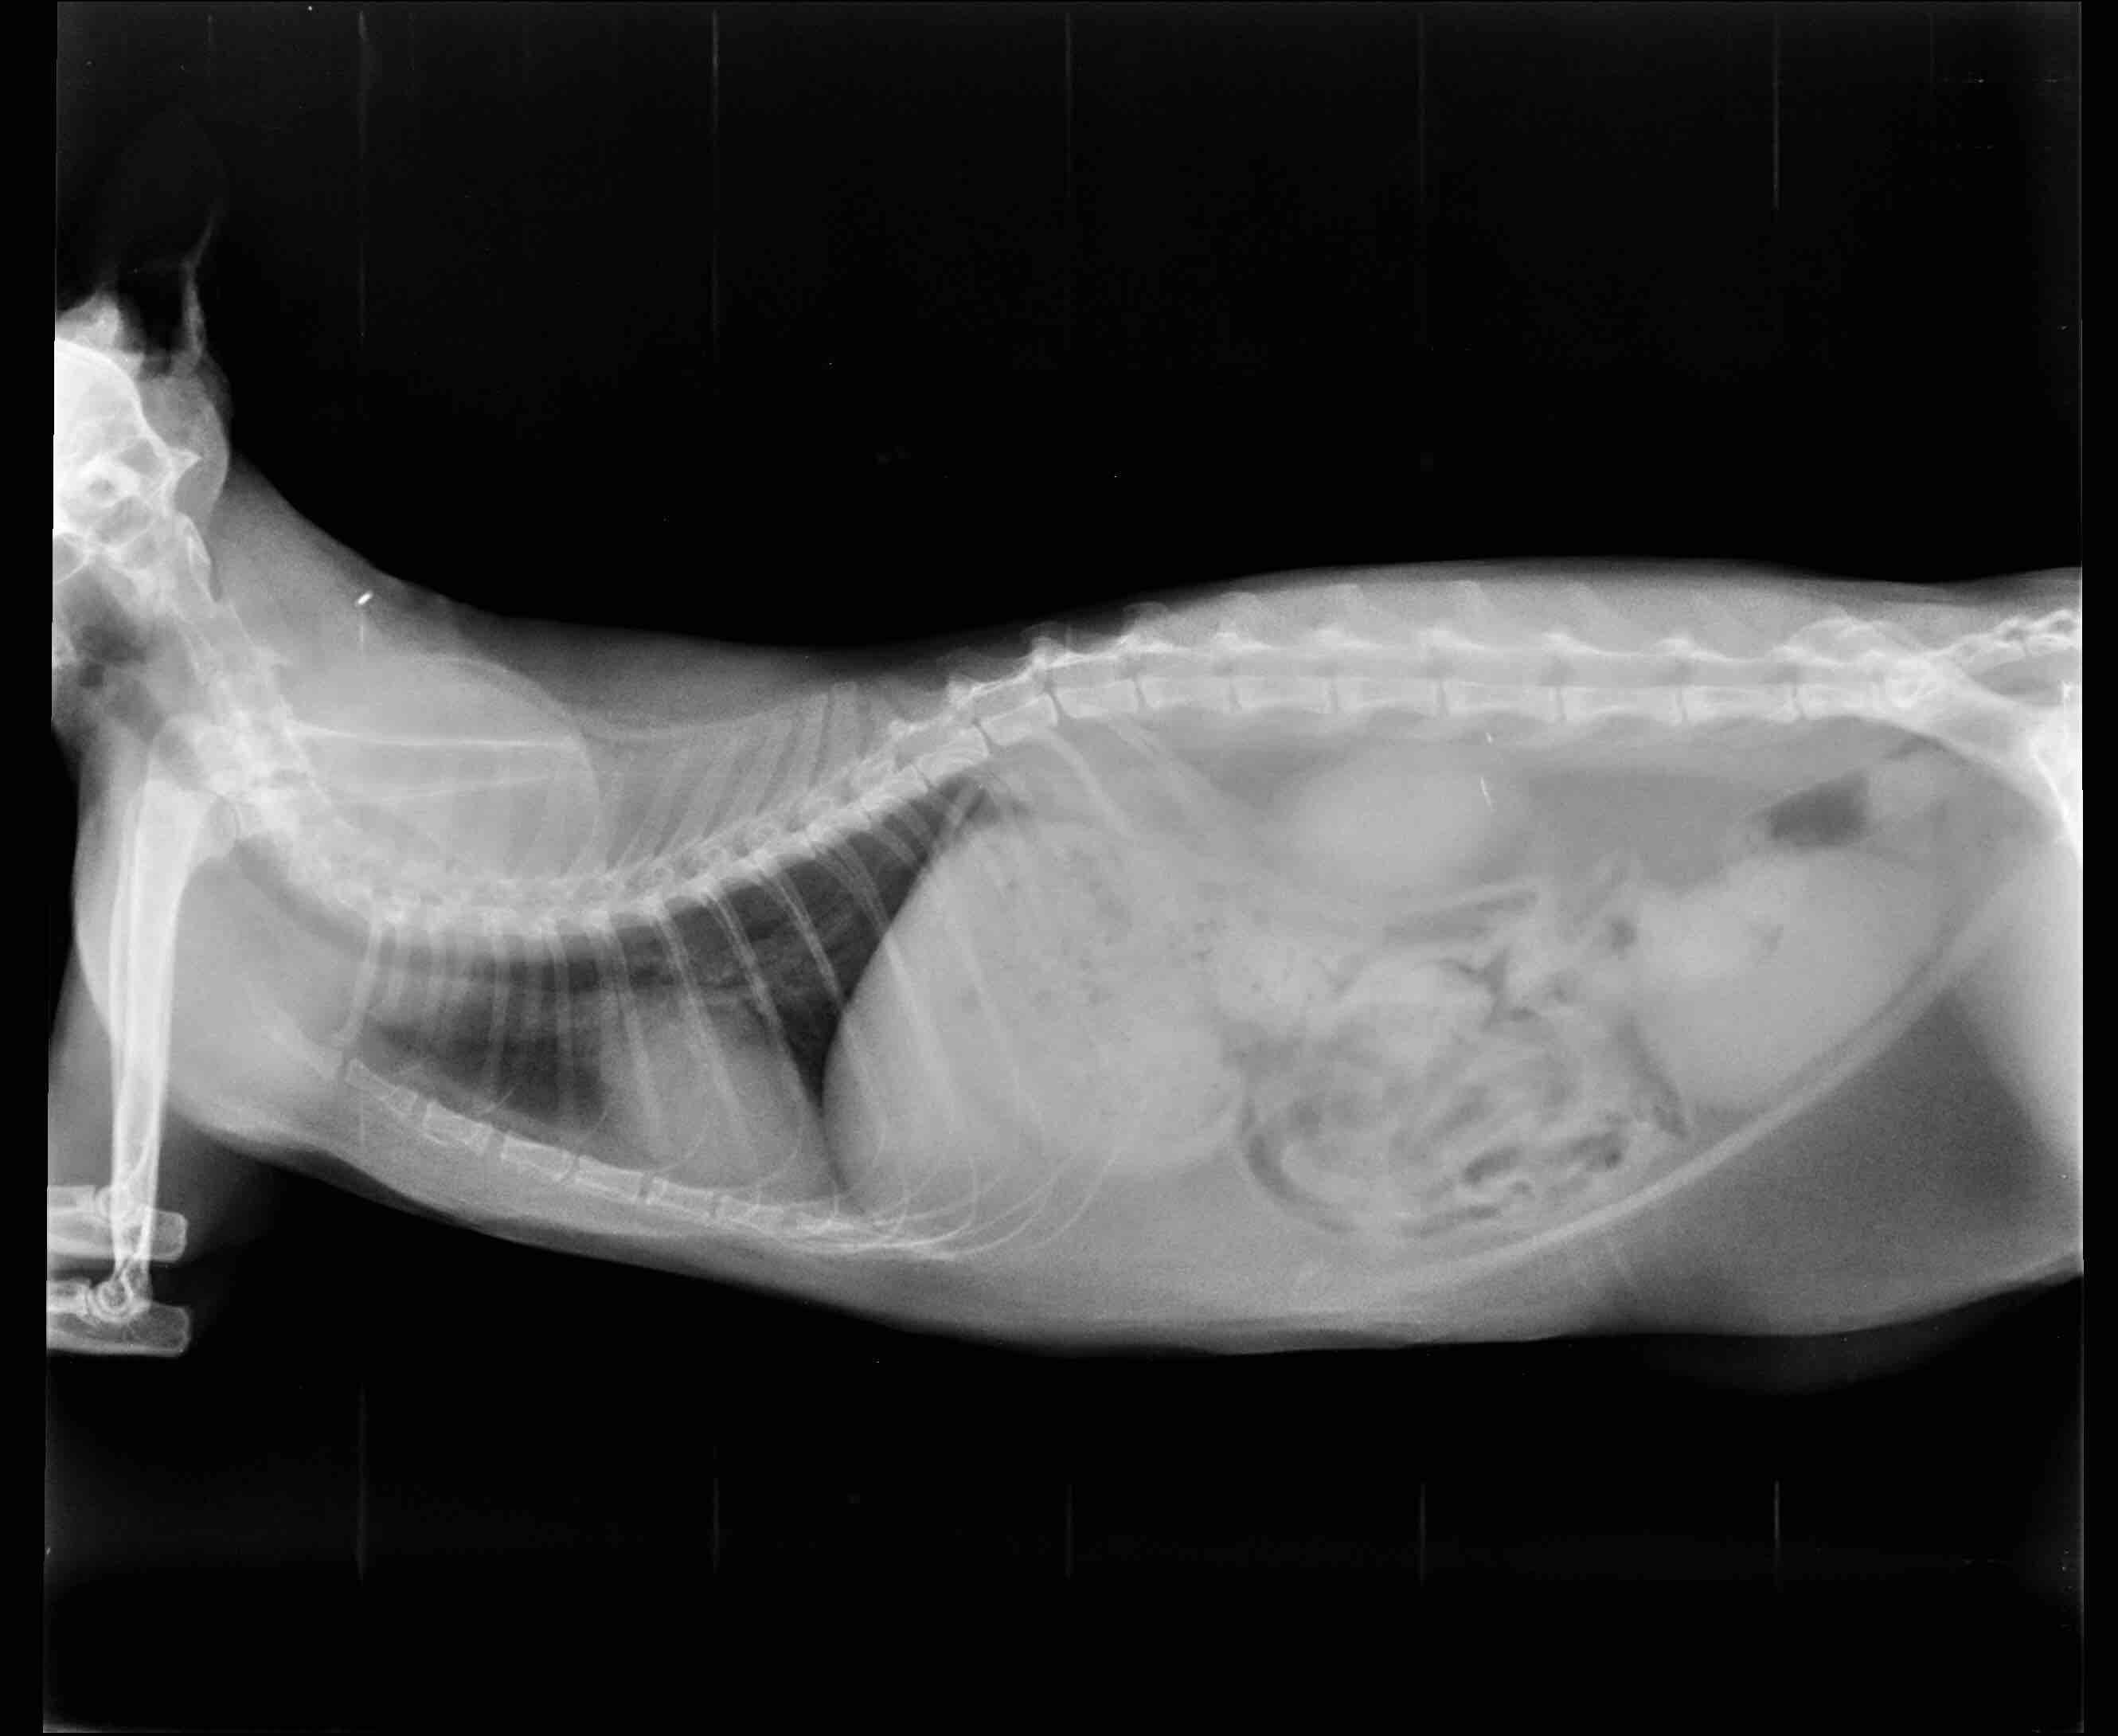

Could you please explain in what ways/way a fast breathing rate of a cat could be related to overweight? Does it mean some sort of serious heart/lung problem or could it just be simple and simply resolved by losing weight?

The excess fat can make breathing harder, and due to that, the cat may breath faster to get sufficient oxygen around the body. The cat's lungs are struggling to inflate with fresh oxygen due to the excess weight, and if the cat doesn't have enough oxygen, they can breath faster to get it. Certainly weight loss can help with breathing problems, but the breathing problems can be caused by heart or lung problems. Only your vet who sees Sofia in person can make this determination. I hope this helps.